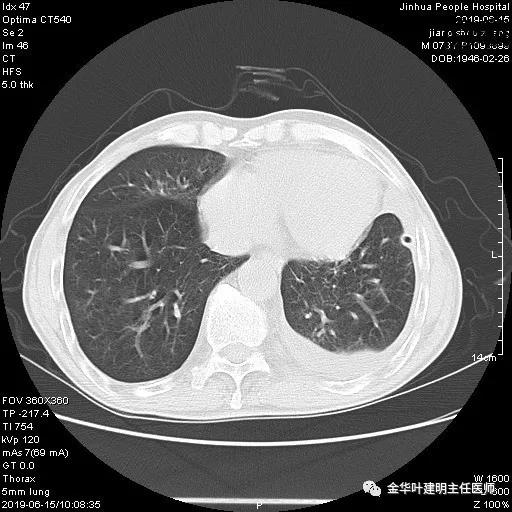

6.15上午:24小时胸管引流出血性液250ml;复查胸部CT示: